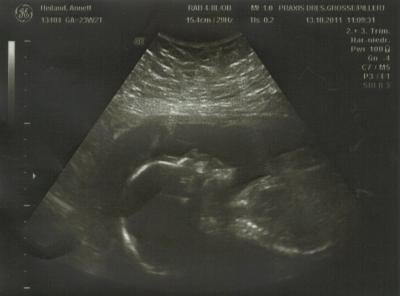

hab ich doch glatt in 4 wochen 4 kg zugenommen. oh je, stehe jetzt gesamt bei +7,6 kg. hatte mir vorgenommen, nicht mehr als 10 kg diese SS zu zu nehmen, aber ich denke das werde ich wohl nicht schaffen, dabei esse ich gar nicht so viel. in der ersten SS hab ich 25 kg und in der zweiten nur 8 kg zugenommen, aber die hab ich ja jetzt schon und es sind ja noch 16 wochen. gebärmutter ist jetzt zwei finger über dem nabel. dann haben wir noch mal versucht, ein schönes 3D bild zu kriegen, aber das war echt unmöglich. hatten wir anfangs gedacht, das die maus ihren arm, bzw. hand über dem gesicht hatte, hat sich nach ca. 10 minuten dann mal raus gestellt, das es nicht der arm, sondern das bein war, was über dem gesicht hängt. wie sie das macht, fragt mich nicht. der fuß war dann knapp hinter dem kopf. also ehrlich, wie geht das bitte??? haben es dann richtig schön gesehen, das bein lang ausgestreckt, so hat sie es sich gemütlich gemacht in meinem bauch, natürlich immer noch in BEL, wie auch sonst. hab dann die FÄ noch mal gefragt, also bis zur 35. 36. woche haben sie noch platz genug zum drehen, bei mehrgebährenden evtl. sogar noch bis eine woche vor der geburt. na dann bin ich ja noch guter hoffnung das sie sich dreht, denn will auf keinen fall einen KS haben. zeig euch mal das bild, leider sieht man es hier nicht so gut drauf, aber wenn man mal etwas links über den kopf kuckt, kann man den fuß erahnen. einfach unglaublich das dass bequem sein kann!!! lg annett

Bild zu hab gerade nen "schreck" bekommen beim FA - Forum für Februar - Mamis